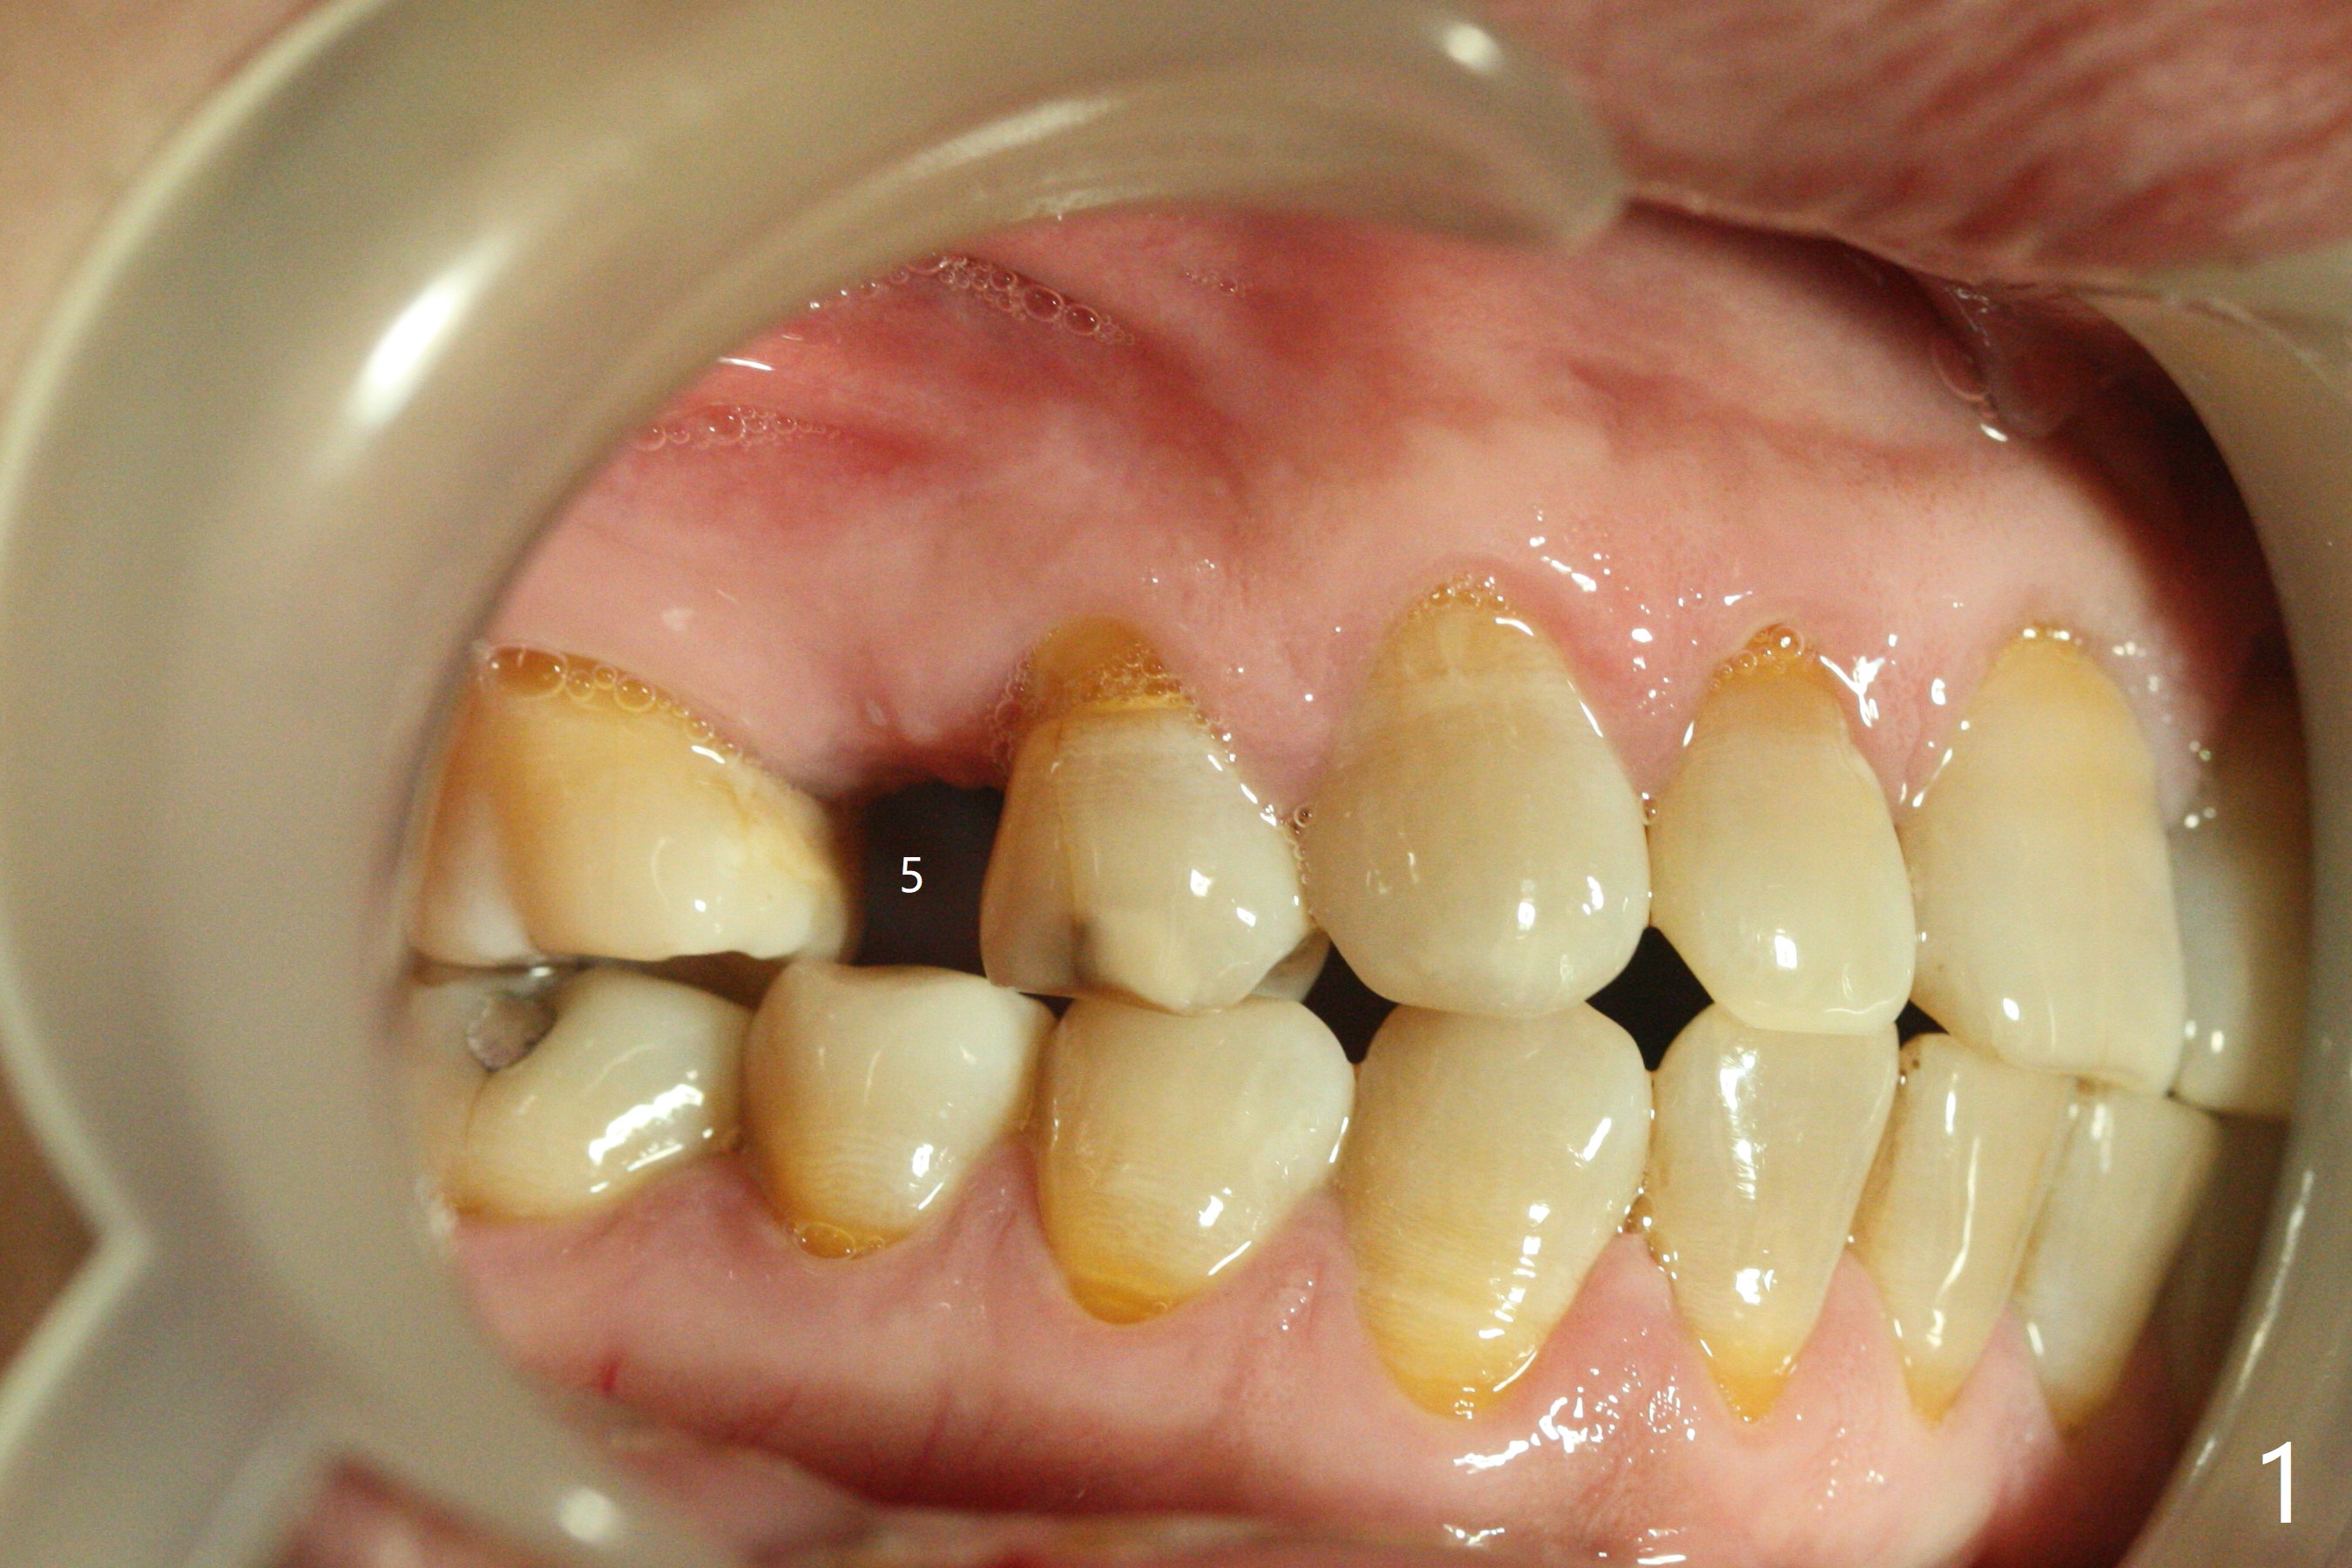

A 40-year-old man requests orthodontics after #17 and 32 extraction. UL5 is missing (Fig.1), while the upper midline deviates to the left (Fig.2 arrow) with crowding between UL2 and 3 (Fig.3). The main goal is to retract UL5 distal and move the upper midline to the right to alleviate UL anterior crowding. Implant will be not needed. To monitor potential root resorption associated with tooth movement, preop PAs are taken (Fig.4-7). The space for an implant at UR5 is narrow. UR4 needs to be distalized using UR7 or a miniimplant distal to UR7 as an anchor (Fig.8). UR4 and 3 will be repositioned to establish Class I occlusion (Fig.9). The space gained by UR4 distalization may be enough to correct the upper midline deviation and UL3 malposition (Fig.10). Brackets will be placed in the lower arch in spite of the normal alignment (Fig.11). UL2 and 3 brackets are unable to be engaged to 14 niti wire (Fig.12). Next visit try to engage UL2 bracket. If not, save the old wire for possible future reuse. Closed spring is placed with 18 ss wire <3 months post banding (coronavirus). Three weeks post closed spring between UR4-7, UR3,4 are being distalized (Fig.13). Distalization of UR4 is not much in 5.5 months (Fig.14,15). It seems necessary to use a miniimplant distal to UR7 as an anchor (Fig.16 white circle), place a long hook mesial to UL4 (more or less root movement instead of tilt) and place the same closed spring between the anchor and hook. In spite of the fact that UR4 seems to have been completely distalized and that UR2 is being distalized 8 months post banding (Fig.18), a 8 mm long mini-implant is placed in the maxillary tuberosity with minimal local anesthetic (Fig.17,19). A longer closed spring (18 mm) is placed between the implant and UR3 hook (Fig.20). Next appointment a lingual button will be placed at UR4 for rotation, while a post hook mesial to UR3 for torque. UR3 distalizes with the help of UR mini-implant, which is unfortunately loose. Next visit place lingual button at UR4 (Fig.21 arrow) to distalize the lingual cusp. Crimpable power hook is placed mesial to UR2 for distalization (for root torque, Fig.22). If it works, remove the wire and reposition the hook for UR1 next visit. UR2 is distalized in one appointment (~ 1 month, Fig.23, as compared to Fig.22). With lingual button at UR4, rotation seems to have been corrected shortly (Fig.24 arrow).